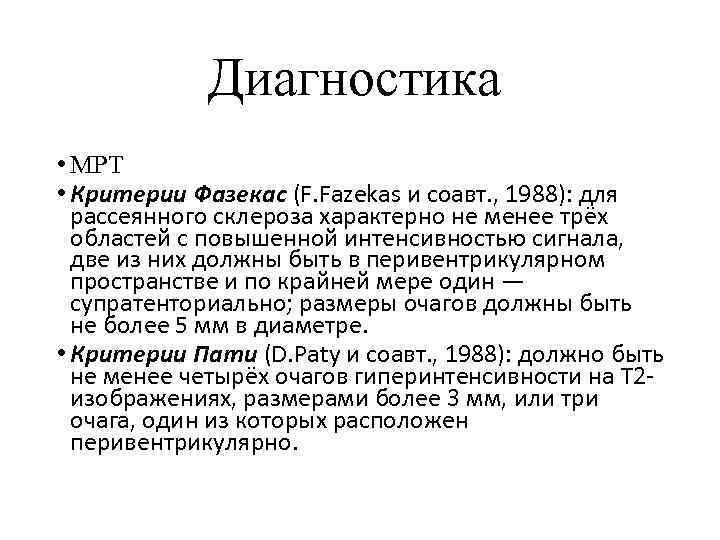

Fazekas grades. Dementia classification. Lesion traumtique cerebral classification.

Fazekas grades. Dementia classification. Lesion traumtique cerebral classification.

Fazekas grades. Фазекас классификация мрт. Лейкоареоз Fazekas 1 что это. Fazekas степени мрт. Лейкоареоз степени по Fazekas.

Fazekas grades. Фазекас классификация мрт. Лейкоареоз Fazekas 1 что это. Fazekas степени мрт. Лейкоареоз степени по Fazekas.

Fazekas grades. Фазекас. Шкала Фазекас мрт. Fazekas классификация мрт. White matter and Gray matter.

Fazekas grades. Фазекас. Шкала Фазекас мрт. Fazekas классификация мрт. White matter and Gray matter.